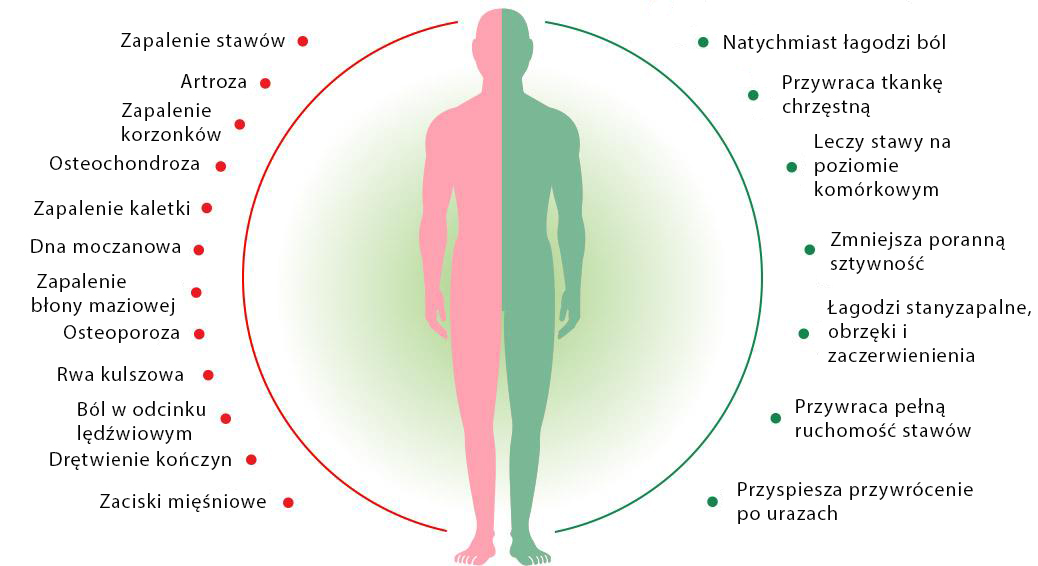

Istnieją tylko 2 główne przyczyny chorób stawów. Te zakłócenia pracy układu odpornościowego i zużycie chrząstki stawowej w wyniku niekorzystnych warunków lub wieku. Jednocześnie nowoczesne preparaty z apteki nie eliminują żadnego z powodów, w przeciwieństwie do olejku z cannabisu. Biologicznie aktywne składniki wzmacniają błony maziowej membrany oraz zwiększają odporność tkanki chrzęstnej, poprawiają krążenie krwi, przyczyniają się do aktywnej regeneracji komórek i odnowy wszystkich tkanek stawowych.

Od 2 lat do odbudowy stawów polecam moim pacjentom tylko olejek z cannabisu. Jego zastosowanie pokazuje po prostu fantastyczne wyniki leczenia. Jeśli chcesz mieć zdrowe, ruchliwe i silne stawy, nawet w podeszłym wieku, polecam spróbować ten wyjątkowy środek.